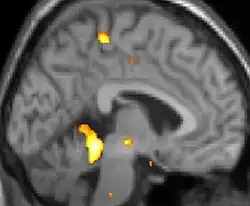

Voxel-based morphometry shows brain area structural differences.

Positron emission tomography (PET) scans indicate the brain areas which are activated during attack only, compared to pain free periods. These pictures show brain areas that are active during pain in yellow/orange color (called "pain matrix"). The area in the center (in all three views) is activated only during cluster headaches. The bottom row voxel-based morphometry shows structural brain differences between individuals with and without CH; only a portion of the hypothalamus is different.[36]